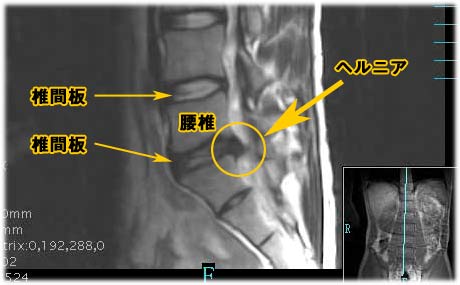

この画像を見る限り椎間板ヘルニアであることは間違いないでしょう。